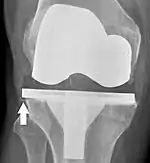

Knee replacement is routinely evaluated by X-ray, including the following measures:

- Anterior femoral notching (the femoral component causing reduced thickness of the distal femur anteriorly), seems to cause an increased risk of fractures when exceeding about 3 mm.[63]

- LTC: lateral (or sagittal) tibial component angle, which is ideally positioned so that the tibia is 0–7° flexed compared to at a right angle with the tibial plate.[62]